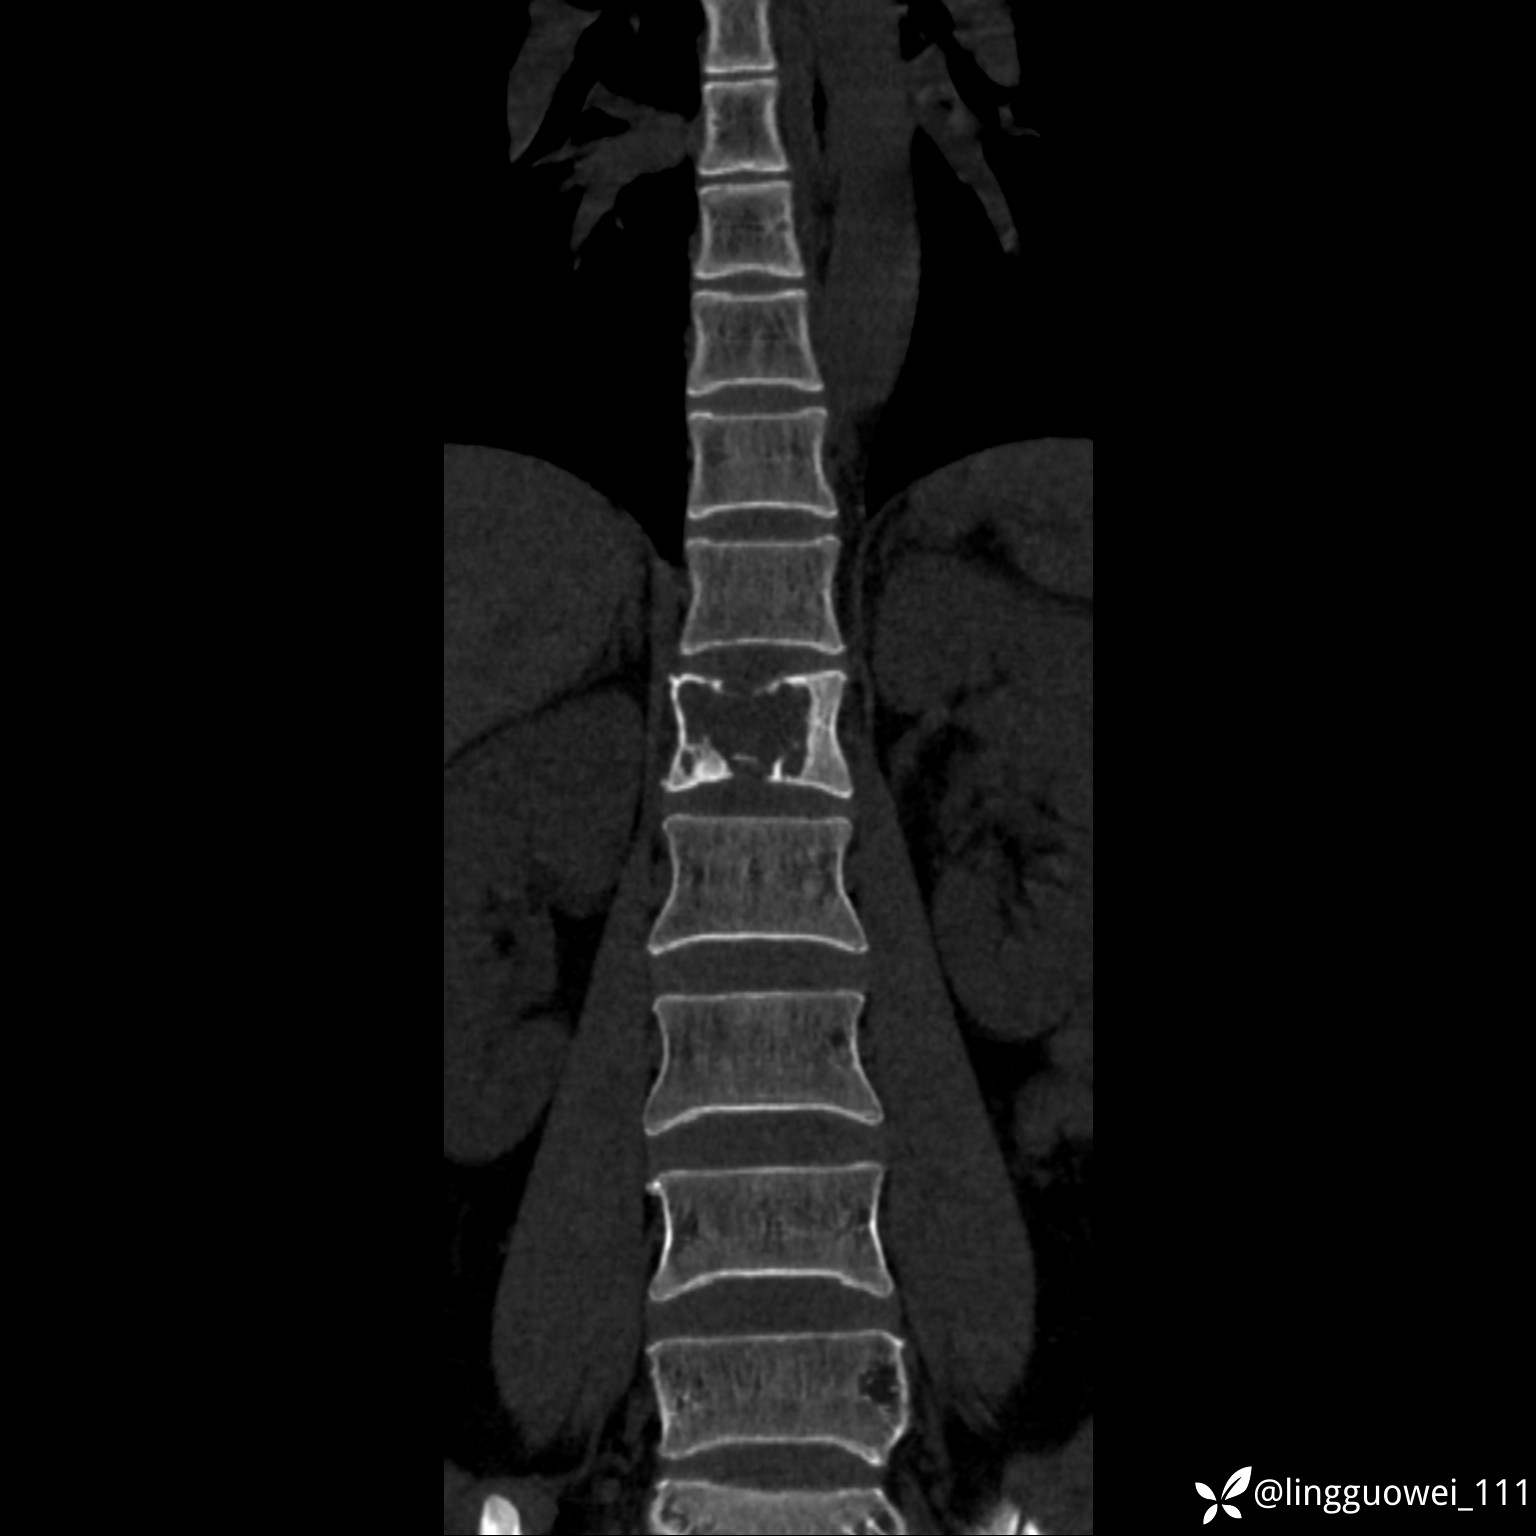

病例女,39岁,腰痛来诊,只有CT可能要鉴别诊断,而MR可以定性吗?

患者性别:女

患者年龄:39岁

主诉:腰痛